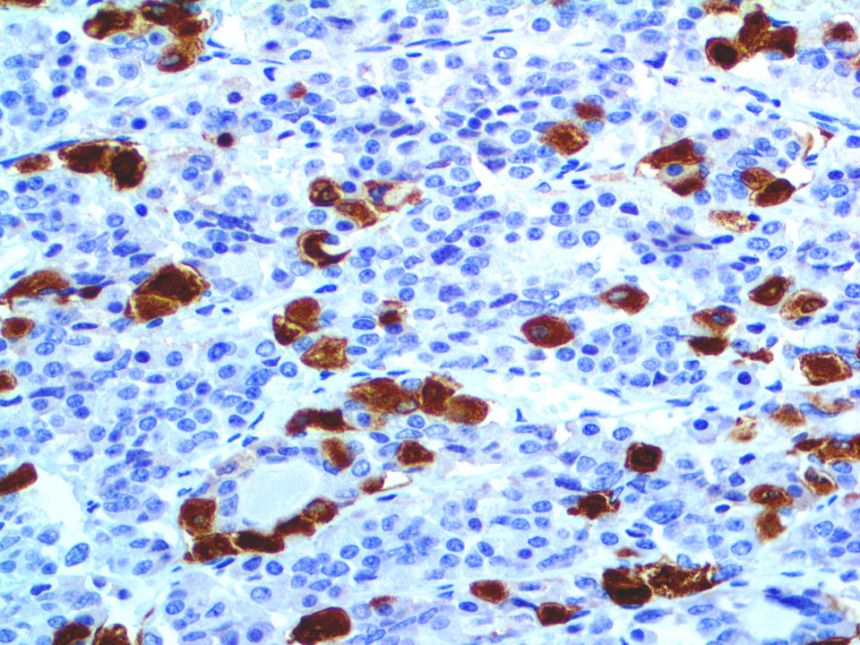

It is the ICU physician who is most likely to witness one of the deadliest manifestations of the abnormal immunological response, the cytokine storm syndrome (CSS). This response is also referred to by some as the cytokine release syndrome (CRS). CSS is characterized by continuous activation and expansion of macrophage and lymphocyte populations, which secrete large amounts of cytokines, causing the cytokine storm. This massive cytokine release is akin to hemophagocytic lymphohistiocytosis (HLH) disease, a syndrome characterized by initial unchecked and persistent activation of cytotoxic T lymphocytes and NK cells.

Clinical and laboratory manifestations of HLH include fever, enlarged liver and/or spleen, neurologic dysfunction, coagulopathy, liver dysfunction, cytopenias (i.e., low levels of erythrocytes, leukocytes, and/or platelets), hypertriglyceridemia, hyperferritinemia, hemophagocytosis, and eventually diminished NK cell activity as the immune system becomes progressively paralyzed. HLH can be familial (primary HLH) or secondary to another disease process (sHLH), such as rheumatic disease, in which it is referred to as macrophage activation syndrome (MAS, characterized by elevated ferritin).